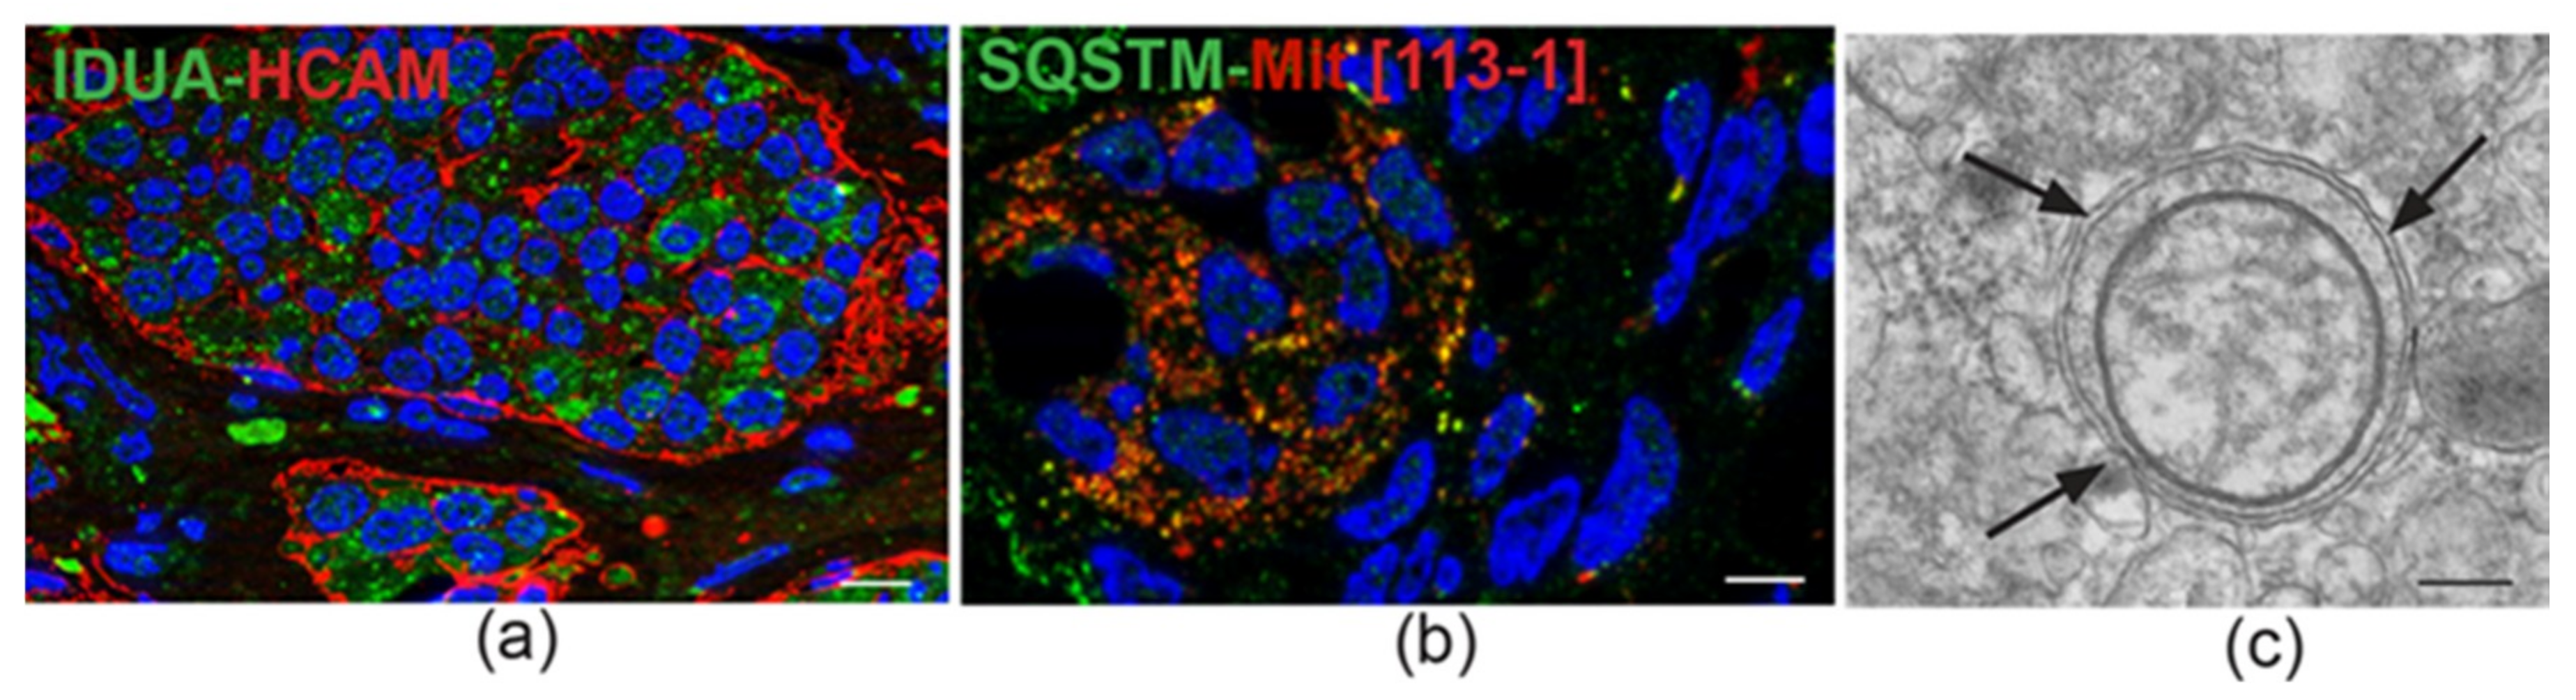

4. Ultrastructural and Immunomorphological Relationships Between the Vascular and Neural Compartments of Head and Neck Paragangliomas

5. Our Approach to the Study of Genes and Pathways Shared Among Head and Neck Paragangliomas